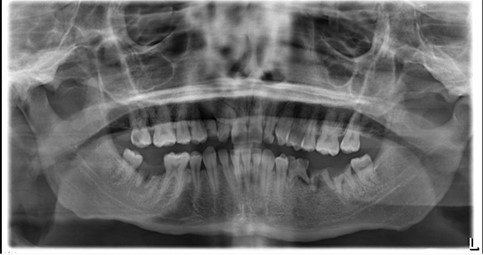

Radiographs taken Monday, 7 February 2022

Justification: OPG was taken to identify caries status, periapical pathology and assess location of ectopic UR3

Grade: diagnostically acceptable

Findings:

- Periapical pathology associated with: LR7, LLE67

- UR3 present, unable to assess position without parallax

- UR7O, URC (distal), UL2M/D, LR6O radiolucencies consistent with caries

- Minimal generalised horizontal alveolar bone loss